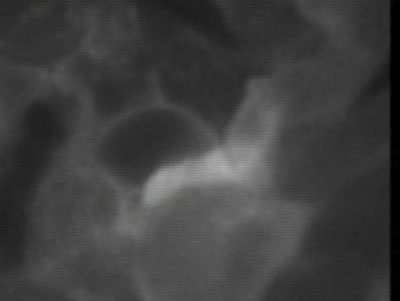

术中吻合